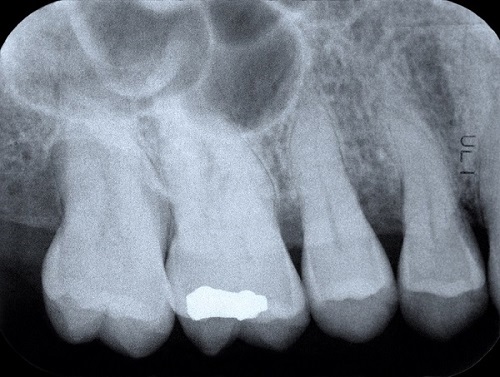

Bite wing x-rays are commonly used as part of dental check-ups. They are commonly used to look for tooth decay and to see how much bone is around the teeth.

An example of a bite wing x-ray. Getty Images.